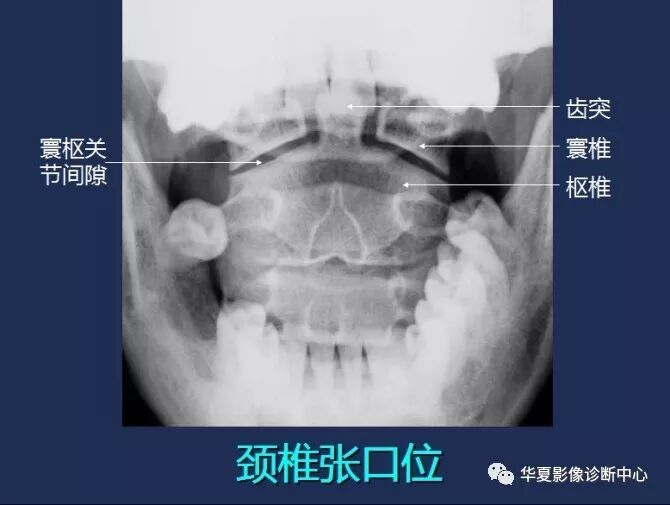

【工作必备】X线解剖图谱+系统解剖(骨骼篇),非常全面,强烈建议收藏~